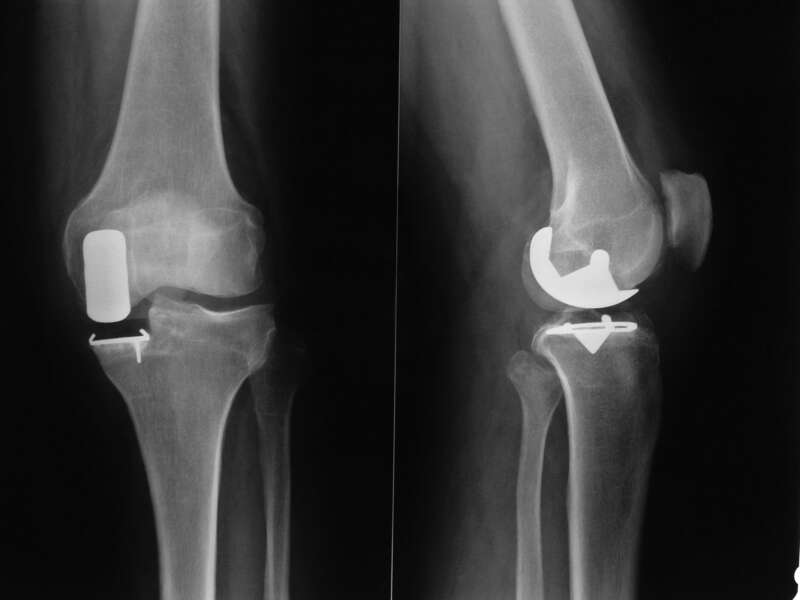

Qu'est-ce qu'une Prothèse uni-compartimentale de Genou?

Cette intervention consiste à remplacer une partie de l’articulation du genou, le compartiment fémoro-tibial interne ou externe, par des composants artificiels qui reproduisent l’anatomie initiale du genou. Le type d’implant doit être adapté à chaque cas particulier, en ce qui concerne sa forme, sa taille, la nature des matériaux entrant dans sa composition, son revêtement extérieur et la technique chirurgicale à employer.

Généralement, une prothèse de genou se divise en deux parties : un insert fémoral et une embase tibiale surmontée d’un polyéthylène. Les composants sont généralement fixés par du ciment.

Album photo